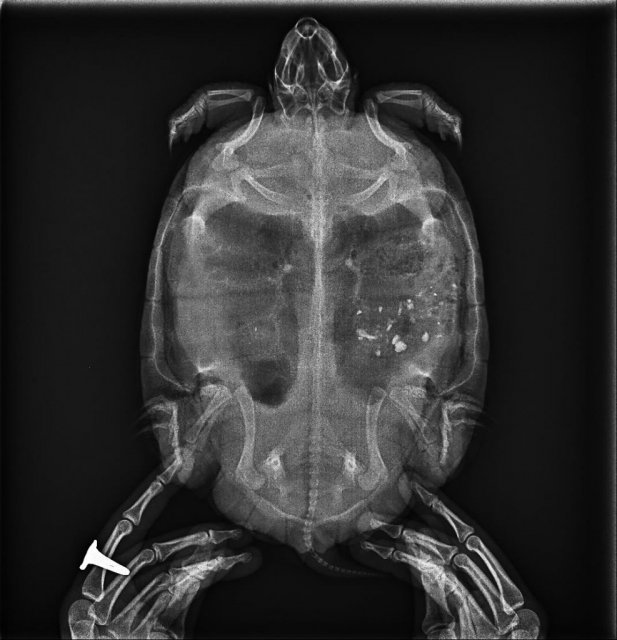

В ветклинике сделали рентген и БАЛ(я не знаю что это), взяли, как я поняла жидкость из легких на бак посев, обнаружили Cytrobacter freundii 10^7. Диагноз бактериальная бронхопневмония и эзофагит. Объяснили, что пищевод с некротическими отлодениями, гиперемирован, а устье трахени отечно с наложениями. Не знаю,  можно ли писать названия антибиотиков, но лучше не буду.  Прописали 2, один уже закончили курс, второй не начали (не по нашей вине),  колем Рингера и делаем ингаляцию. В 60 л воды добавили мителеновый синий.

а ничего не говорили про что-то рентгеноконтрасное на снимках в теле? у неё никогда грунта не было?

@moth Первый рентген был такой.  Думаем, пообдирала камушки со старого аквариума. Сейчас грызла искусственную траву, но понемногу интерес к ней угасает. На этот раз ничего про рентгеноконтрастное не говорили, надеюсь,  тоже выйдет естественным путем. Понаблюдаем за ней.

1152.144.1188.1178.157.10.20231205093737.3.jpg

@nrthdr да, тогда это остатки камней